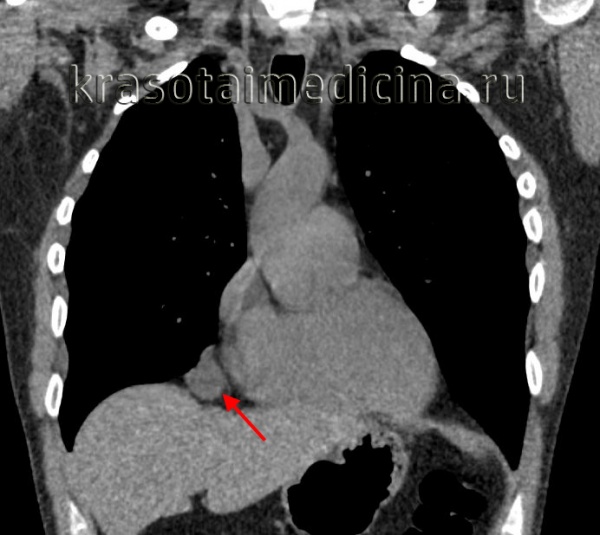

Полость бронхогенной кисты средостения изнутри выстлана эпителием цилиндрического или реснитчатого типа. Внутри кисты содержится прозрачная или мутноватая желатинообразная, вязкая масса, которая, при наличии связи кисты с бронхиальным деревом, может нагнаиваться. Бронхогенные кисты средостения обычно располагаются позади бифуркации трахеи и тесно соприкасаются с трахеей или главными бронхами, иногда - пищеводом. Обычно они имеют однокамерное строение и достигают размеров 7-10 см в диаметре.

Развитие бронхогенных кист средостения нередко сопровождается надсадным кашлем, одышкой, дисфагией, тупой болью в грудной клетке. При сдавлении кистой дыхательных путей развивается стридорозное дыхание. В случае прорыва бронхогенной кисты средостения в бронх может появиться кровохарканье. При одновременном прорыве кисты в плевральную полость и в бронх, развивается гидропневмоторакс и бронхоплевральный свищ.